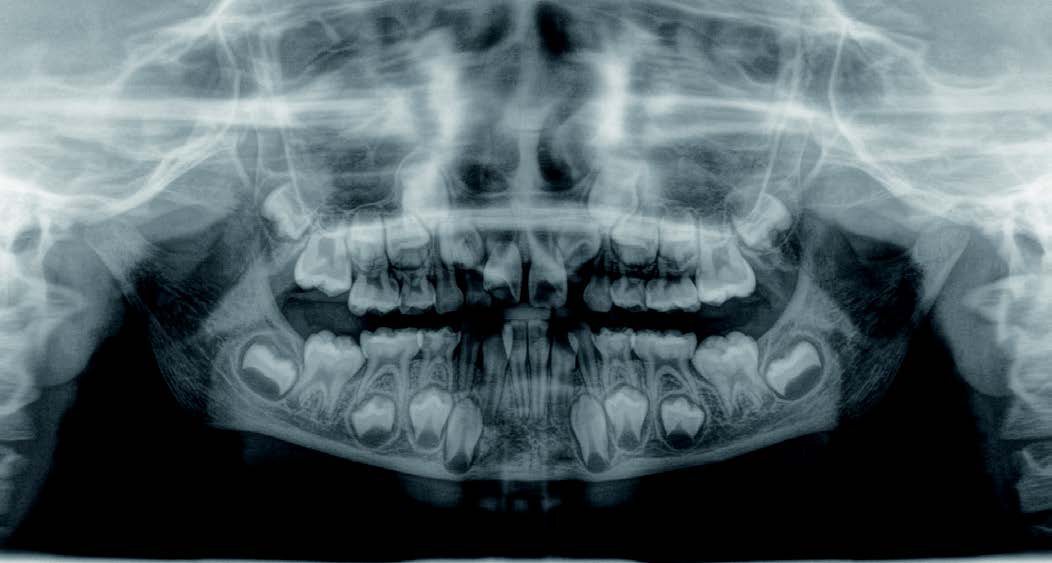

出っ歯

「本当に永久歯を抜かずに治るの?」半信半疑で相談に来られました

Mさん (矯正開始時:8歳)

Before

After

これから生えてくる永久歯のスペースがなく、歯が並ぶ余地がほとんどありませんでした。

さらに、上からあごの骨を見たところ、中央がくびれた“ひょうたん型”に変形しており、あごの成長にも偏りが見られました。

診断の結果、前歯の中心も少し左にずれており、特に犬歯が生えるスペースが足りない状態でした。

飲み込むときに下くちびるに力が入り、顔の左側にゆがみが出ている様子も確認できました。

治療を終えて

犬歯が歯ぐきの中に埋まっていたため、透明のマウスピース型装置で生えるスペースを作り正しい位置に導きました。もちろん抜歯せずに歯並びを整えることができました。お口の中がとても小さく、型どりの際にオエッとなる反応が強く、当時は装置を作るのが大変でした。しかし現在では3Dスキャナーと3Dプリンターを活用しスムーズに治療できます。

主訴・治療内容 「あごが小さいから、歯がきれいに並ばない」と他院で言われ永久歯を抜く矯正をすすめられていました。

本当に非抜歯で治療できるのか心配されていましたが、治療方法を丁寧にご説明し、お任せいただきました。

治療期間 5年

費用 550,000円(税込)